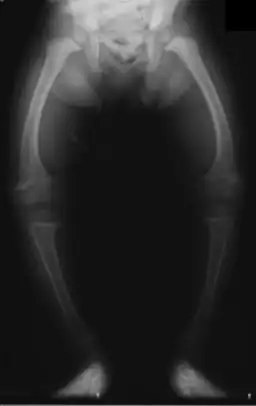

| Significant bilateral nephrocalcinosis (calcification of the kidneys) on a frontal X-ray (radiopacities (white) in the right upper and left upper quadrant of the image), as seen in distal renal tubular acidosis | |

- Nephrocalcinosis (deposition of calcium in the substance of the kidney)